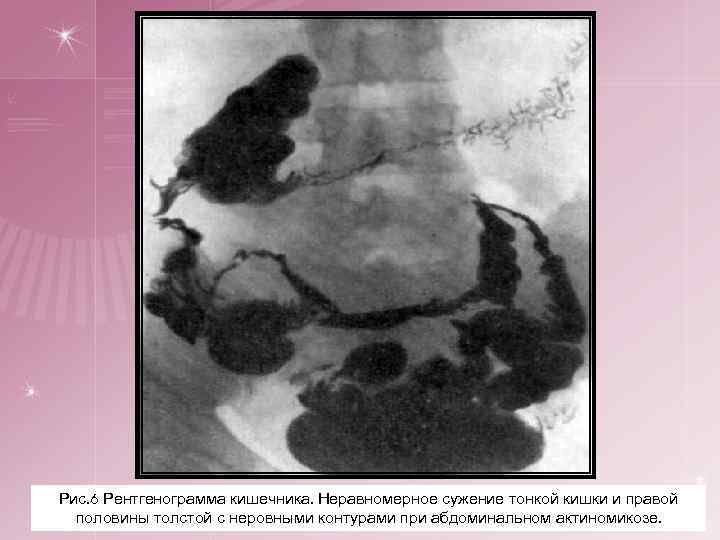

3. Абдоминальный актиномикоз. § Первичные очаги чаще локализуются в илеоцекальной области и в области аппендикса (свыше 60%), нередко имитируя хирургические заболевания (аппендицит, непроходимость кишечника и др. ). Затем идут другие отделы толстой кишки и очень редко поражается первично желудок или тонкий кишечник, пищевод. § Распространяясь, инфильтрат захватывает и другие органы: печень, почки, позвоночник, может достигнуть брюшной стенки. § Брюшная стенка поражается вторично. Возникают характерные изменения кожи, свищи, сообщающиеся с кишечником и расположенные обычно в паховой области. § При актиномикозе прямой кишки инфильтраты обусловливают возникновение специфических парапроктитов: свищи вскрываются в перианальной области.

Рис. 6 Рентгенограмма кишечника. Неравномерное сужение тонкой кишки и правой половины толстой с неровными контурами при абдоминальном актиномикозе.